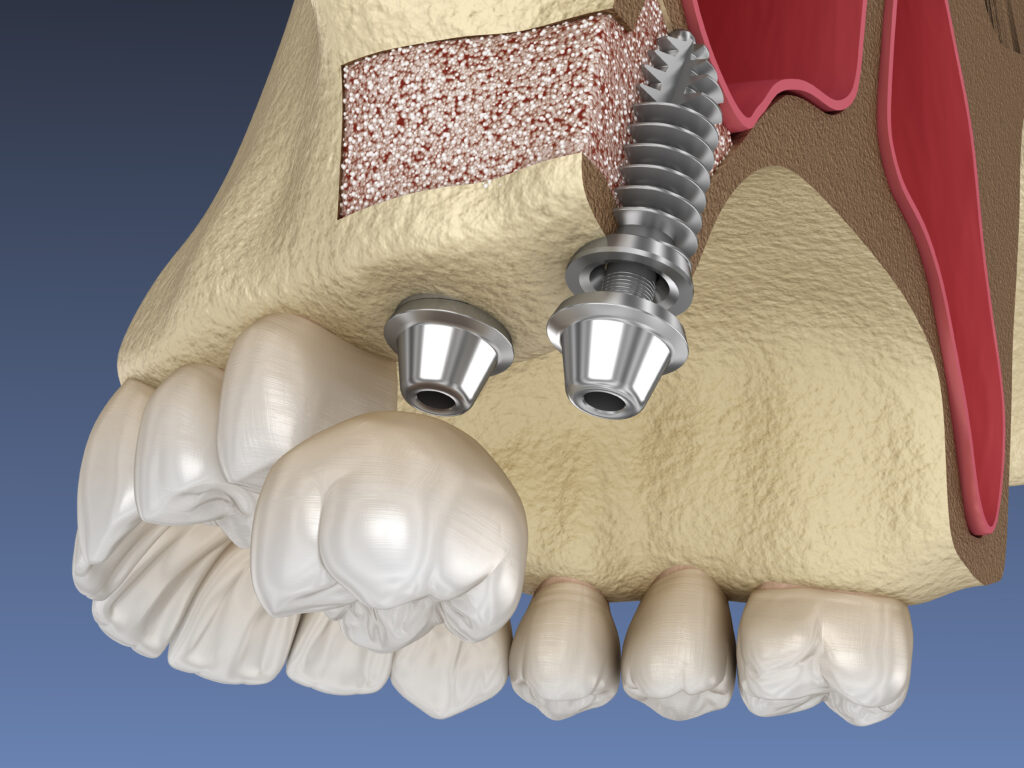

Bone grafting

Bone grafting in dentistry is a surgical procedure aimed at restoring the volume of the jaw bone required for dental…

Learn more

Step 4 — Prosthetics and Orthodontics Integration

After the initial healing process is complete, we proceed with the restorative phase, which might involve implant placement and the final placement of an abutment and artificial teeth. This ensures proper osseointegration and function.